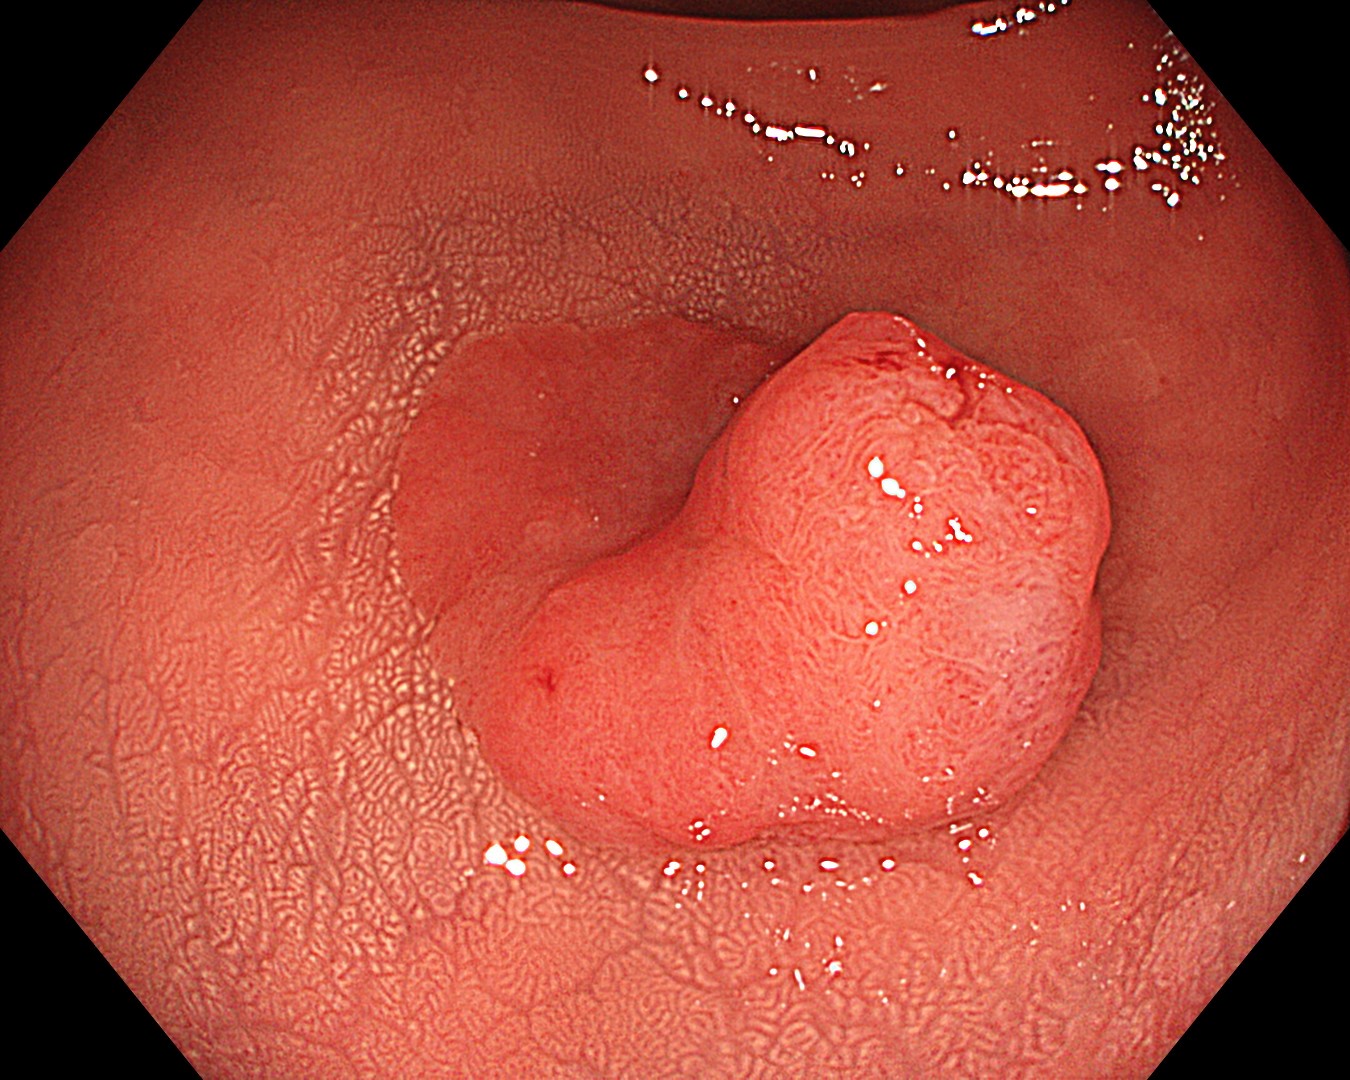

• 白色光観察①(中遠景)

強調設定:A8

図1

白色光観察で、下部直腸に20mm大の境界明瞭で発赤調の隆起性病変を認めた。病変は、丈の高い隆起部と平坦隆起部からなる 0-Is+IIa病変として認識された。周囲粘膜に白斑を伴っており、腺腫~大腸癌が疑われた。